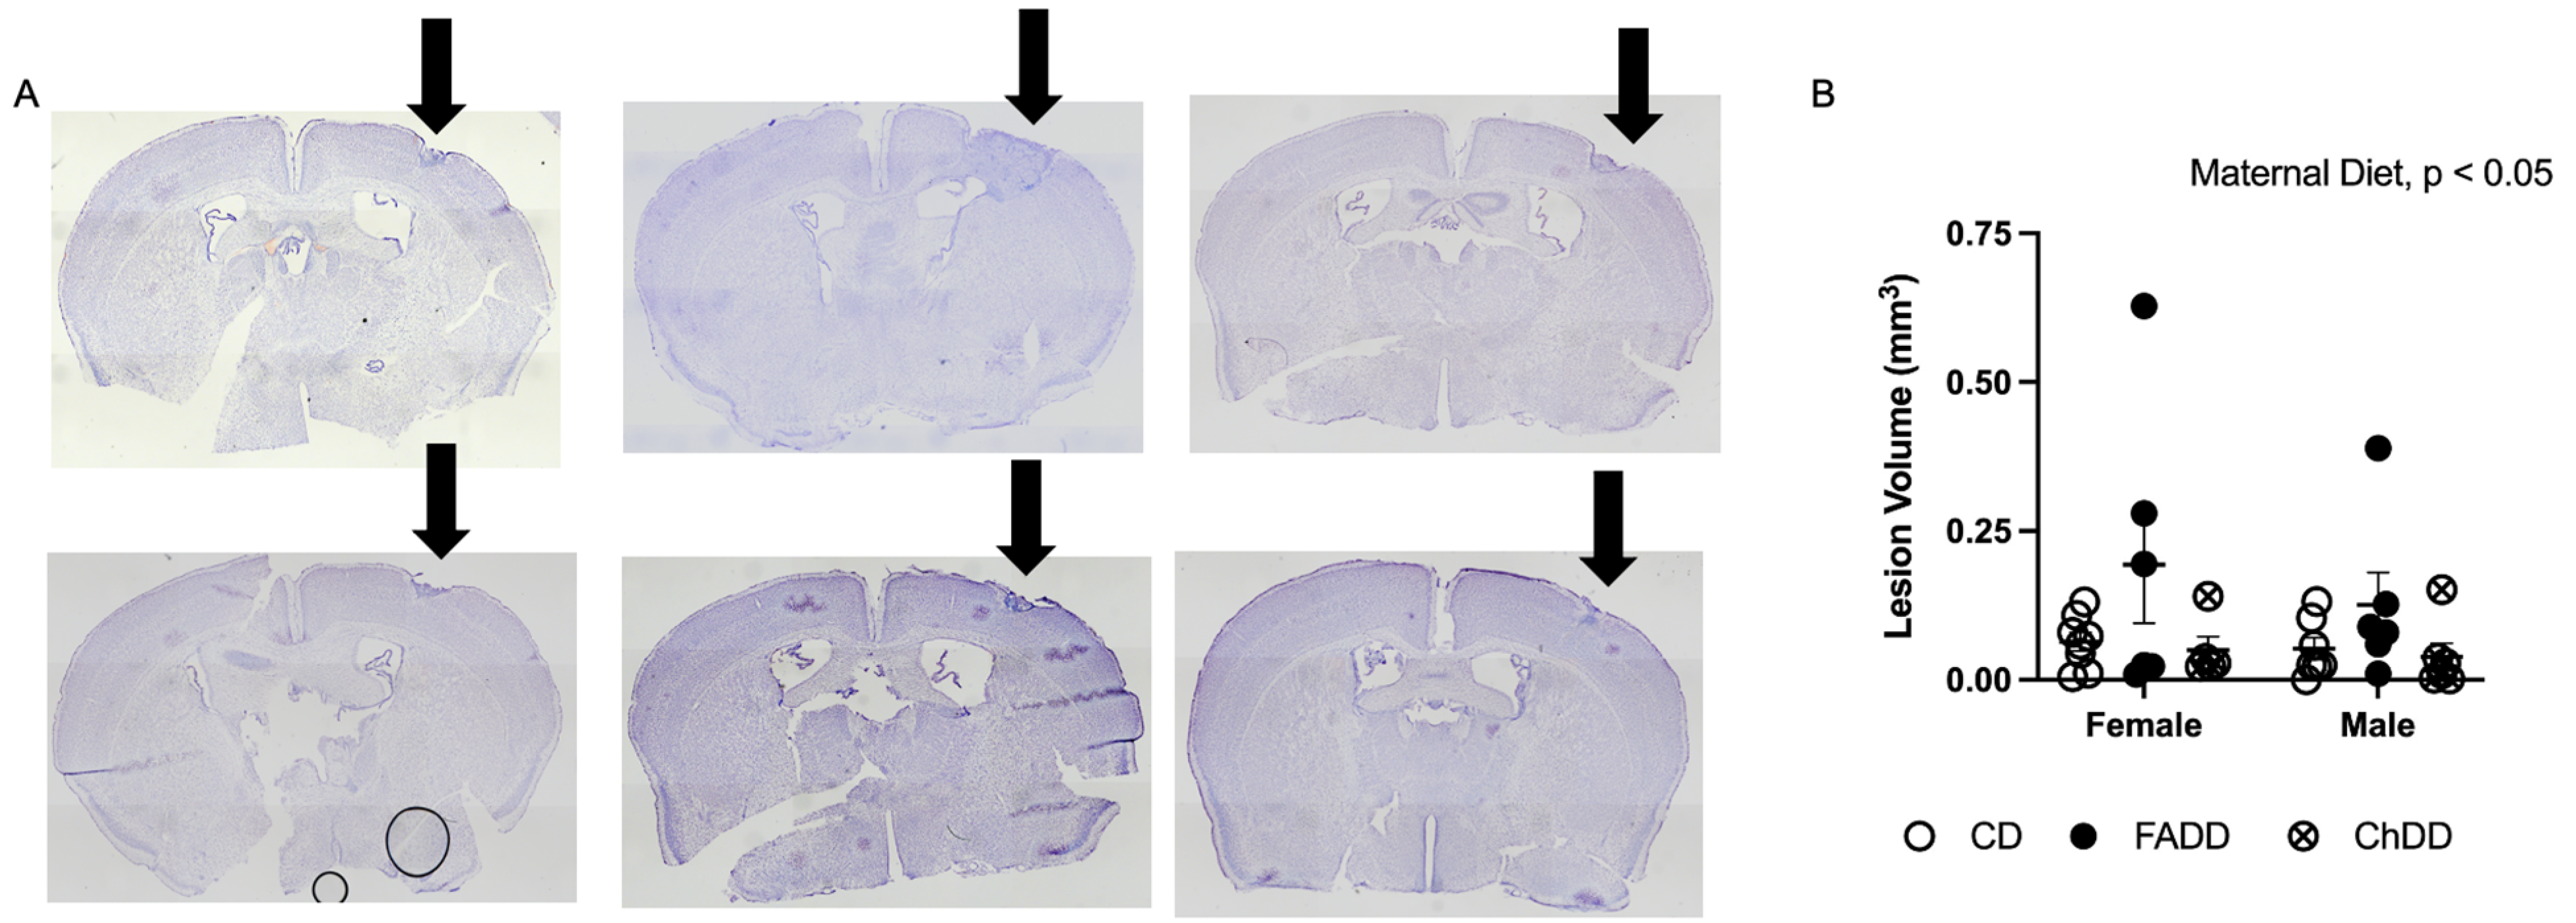

3.4. Ischemic Damage Volume Increased in Offspring as a Result of Maternal Dietary Deficiencies